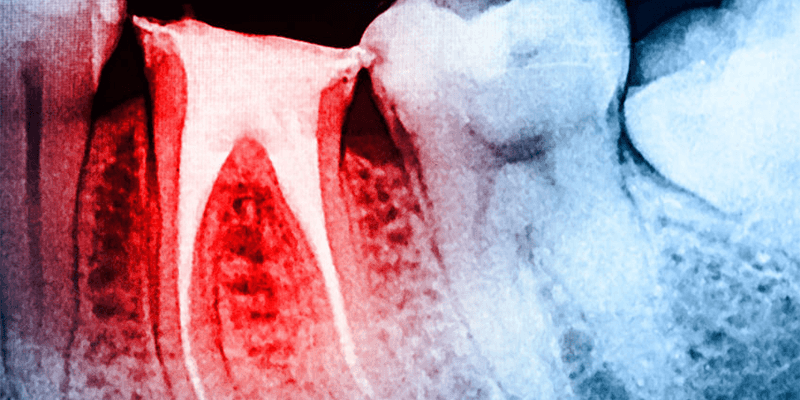

Eine gute uns regelmäßige Zahnhygiene und Prophylaxe-Besuch beim Zahnarzt sind nicht nur für die Verhinderung von kariesbedingten Zahnlöchern und ein gepflegtes Äußeres wichtig. Die Bakterien im Mundraum können sich nämlich auch durch den Zahn oder das Zahnfleisch bis zur Wurzel fressen und irreparable Schäden anrichten. Die Bakterien sondern Giftstoffe und Säuren ab, die sie besonders aus Zucker herstellen können. Die Säuren greifen den Zahnschmelz an und lösen Mineralien aus der Oberfläche (Karies). In die so entstandenen Mulden setzen sich daraufhin vermehrt Bakterien ab und beginnen systematisch den Zahnschmelz zu zerstören. Wird dieser Prozess nicht rechtzeitig gestoppt, indem das Loch gesäubert und mit einer Füllung verschlossen wird, erreicht der Karies die Wurzeloberfläche und schließlich das Zahnmark, in dem die Versorgungsgefäße und der Zahnnerv sitzen.

Gleiches kann beim Rückgang des Zahnfleisches (Parodontose) geschehen, die Bakterien gelangen nicht durch den Zahnschmelz hindurch zur Wurzel sondern das Zahnfleisch wird durch die Giftstoffe der Bakterien beeinflusst. Dieses entzündet sich und kann bei Nichtbeachtung soweit zurückgehen, dass der Zahnhals freiliegt. Nun gelangen die Kariesbakterien ungehindert zur Wurzel und können dort ihr zerstörerisches Werk fortführen. Spätestens dann verursacht der Kariesbefall starke Schmerzen, sobald sie den Nerv freigelegt haben. Nun entzündet sich meist das Zahnmark, also das gesamte Gewebe im und um den Zahn.

Das entstandene Loch ist außerdem nicht mehr mit der Zahnbürste zuhause zu reinigen. Auch Mundwasser reicht nicht aus, die Zerstörung durch Ausspülen der Bakterien aufzuhalten. Ein Zahnarztbesuch ist unvermeidlich. Je zuverlässiger sich der Patient schon vorher regelmäßig untersuchen lässt, desto schneller kann das noch kleine Loch entdeckt werden und Schmerzen weitestgehend verhindert werden. Erreicht der Karies die Wurzel kann oft nur noch mit einer klassischen Wurzelbehandlung reagiert werden, bei der das Loch ausgebohrt wird, um einerseits alle Bakterien zu entfernen, andererseits jedoch, um das befallene Gewebe samt Nerv auszuschaben und den Bereich steril zu machen.